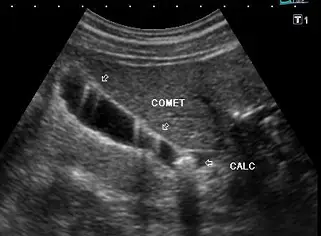

當超音波掃描膽囊時,呈現如附圖的彗尾假影( comet tail ),其最有可能的病變為何?

提供的影像為膽囊的灰階超音波掃描圖,可觀察到以下幾項重要特徵:

- 影像中標示「COMET」的兩個箭頭,指向膽囊前壁內的數個高回音(hyperechoic)亮點。

- 這些亮點的後方伴隨著呈V字型、向下延伸且逐漸變窄的強烈回音帶,這正是典型的彗星尾假影(comet tail artifact)。

- 產生此假影的區域,可明顯觀察到膽囊壁呈現局部增厚。

- 影像右下方另有標示「CALC」的箭頭,指向膽囊頸部或底部的一個強回音結構,其後方伴隨明顯的後方聲影(posterior acoustic shadowing),這代表患者同時合併有膽囊結石(gallstone / calculus)。